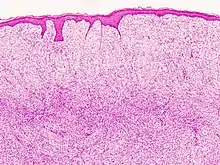

![]() | |

| Histopathological image of dermatofibrosarcoma protuberans. Local recurrence long after the first excision. H&E stain | |

Monotonous, plexiform structure of tumour